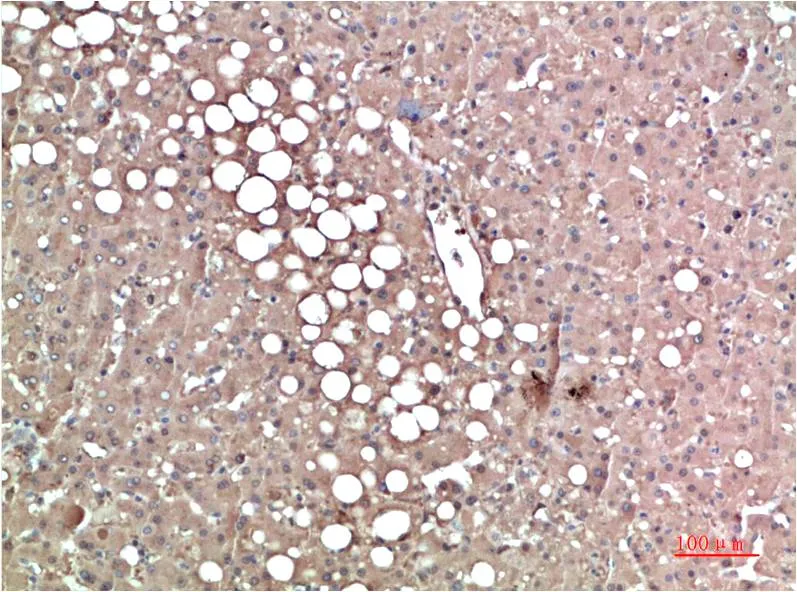

Prealbumin (1F6) Mouse Monoclonal Antibody

Cat: AMM00893

Size1:50μl Price1:$150

Size2:100μl Price2:$280

Size3:500μl Price3:$1200

Size2:100μl Price2:$280

Size3:500μl Price3:$1200